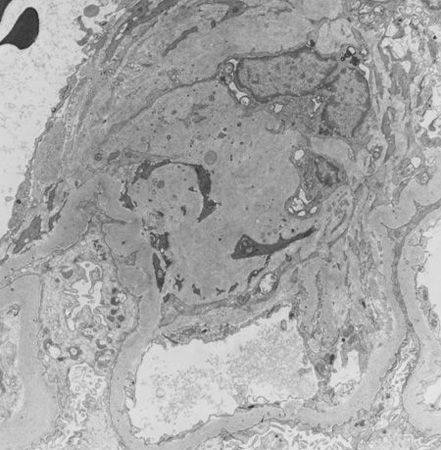

Diabetic kidney disease

Diabetic kidney disease: at 12 o'clock - early Kimmelstiel-Wilson nodule, a rounded form of mesangial expansion

From the collection of Dr Raoul Fresco; used with permission